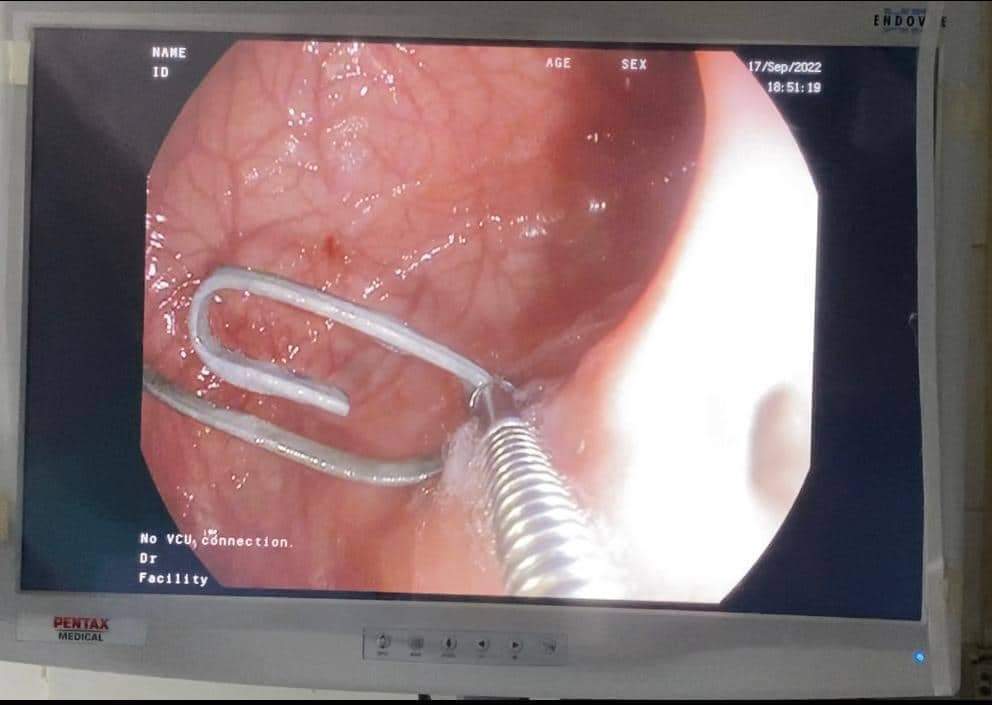

وتمكن فريق العمل بوحدة الجهاز الهضمي والكبد بمستشفي الأطفال الجامعي بالمنصورة بقيادة الدكتور محمد عز رئيس الوحدة وبمساعدة الدكتورة دعاء فهمي مدرس طب الأطفال وقسم التخدير ممثلا فى الدكتور احمد عبد اللطيف من إزالة 5 دبابيس معدنية يتراوح طول الدبوس الواحد حوالي 3 سم من مرئ ومعدة طفل يبلغ من العمر ثلاثة أشهر.

وتم التشاور مع قسم جراحة الأطفال تحت قيادة ا الدكتور أدهم السعيد ومساعدة الدكتور محمد البشبيشي مدرس جراحة الأطفال ونجح فريق العمل بعمل منظار معدة للطفل واستخراج الدبابيس المعدنية بسلام.

وقال الدكتور محمد عز رئيس الوحدة أن هذه الحالة تعد من الحالات الصعبة نظرًا لعمر الطفل ووجود عدد كبير من الدبابيس ذات الأطراف الحادة التي تحتاج لمهارة عالية في إستخراجها.